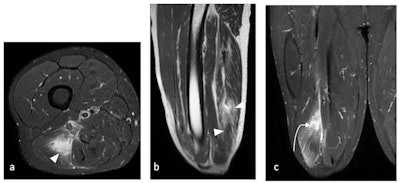

Biceps femoris muscle tear in a 35-year-old male footballer. (a) Axial T2-weighted fat-saturated, (b) Sagittal T2-weighted, and (c) Coronal T2-weighted fat-saturated MRI of pelvis demonstrates interstitial edema within the long head of the biceps femoris muscle (white arrowheads) with an area of fluid-signal intensity (white curved arrow). Note the interruption of the muscle and intramuscular tendon, representing muscle laceration reaching the medial myofascial surface. All images courtesy of Dr. Cleofina Furtado, Dr. Rania Zeitoun et al, and EPOS/European Society of Radiology (ESR)."Pelvic apophyseal injuries are common in young football players," stated Furtado and Zeitoun. "Apophyses, bony attachments of the tendons, are a common site of acute avulsion secondary to forceful muscle contraction. This might affect the anterior superior iliac spine, anterior inferior iliac spine, ischial tuberosity, iliac crest, and pubic bones, as well as the greater and lesser trochanters of the femur."